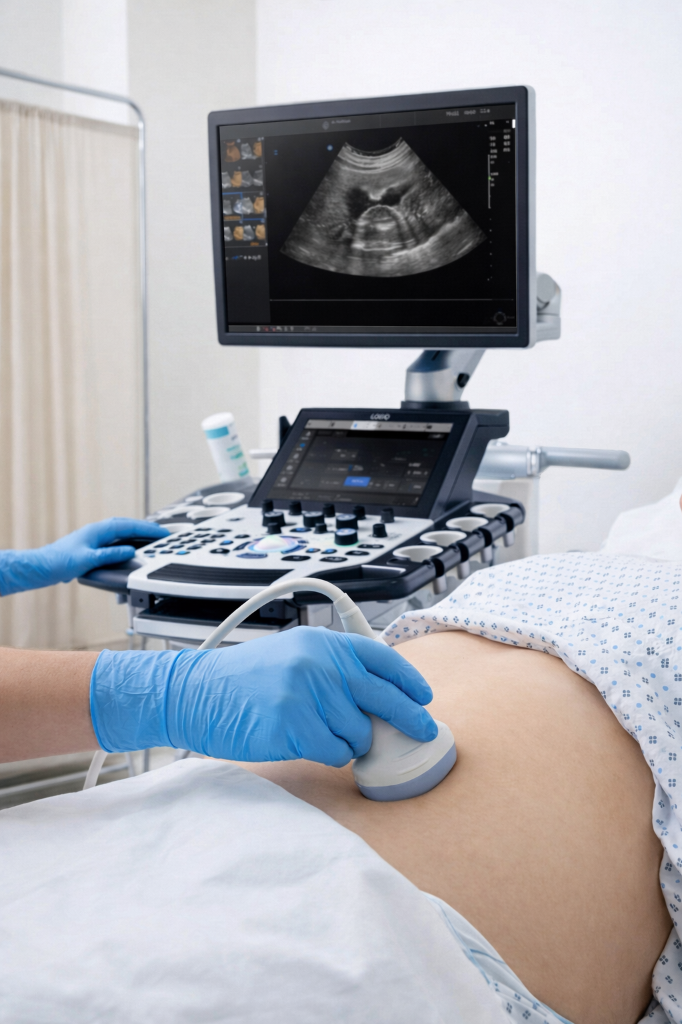

초음파 주사

Ultrasound Injection

X-ray에서 확인할 수 없는 미세한 골절이나 연부 조직의 손상을 초음파 유도하에 진단하고 치료하는 방법입니다.

불필요한 방사선의 노출을 피할 수 있어 어린이, 임산부, 고령의 기저질환자도 부담 없이 진단할 수 있으며

통증 부위 및 구조를 실시간으로 확인하며 주사하므로 정확한 시술로 효과가 뛰어나고 소량의 주사액을 사용할 수 있어 부담이 적습니다.

미세 골절 및 연부 조직 손상 정밀 진단

방사선 노출 없어 임산부·노약자도 안전

실시간 확인으로 정확한 시술 및 약물 최소화